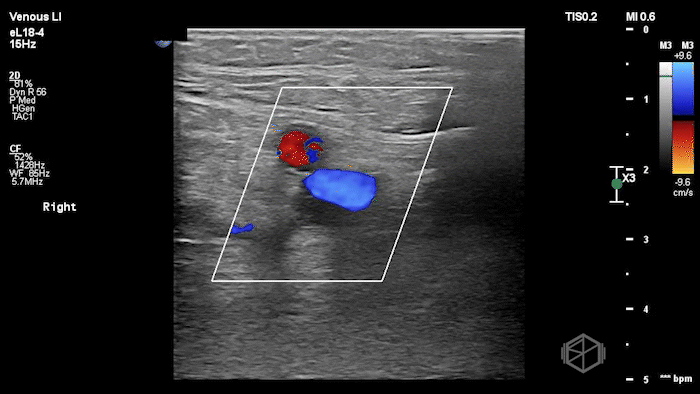

A lower extremity DVT ultrasound performed by Dr. Koutsounadis demonstrated the following:

The POCUS shows a right common femoral vein thrombus. Family members reported that the patient had previously been diagnosed with a DVT very recently and was on apixaban.

The thrombus appeared predominantly hypoechoic to nearly anechoic, making it difficult to appreciate on B-mode imaging alone. However, incomplete compressibility of the vein confirmed the presence of thrombus.

Diagnosis: Right common femoral partially occlusive DVT